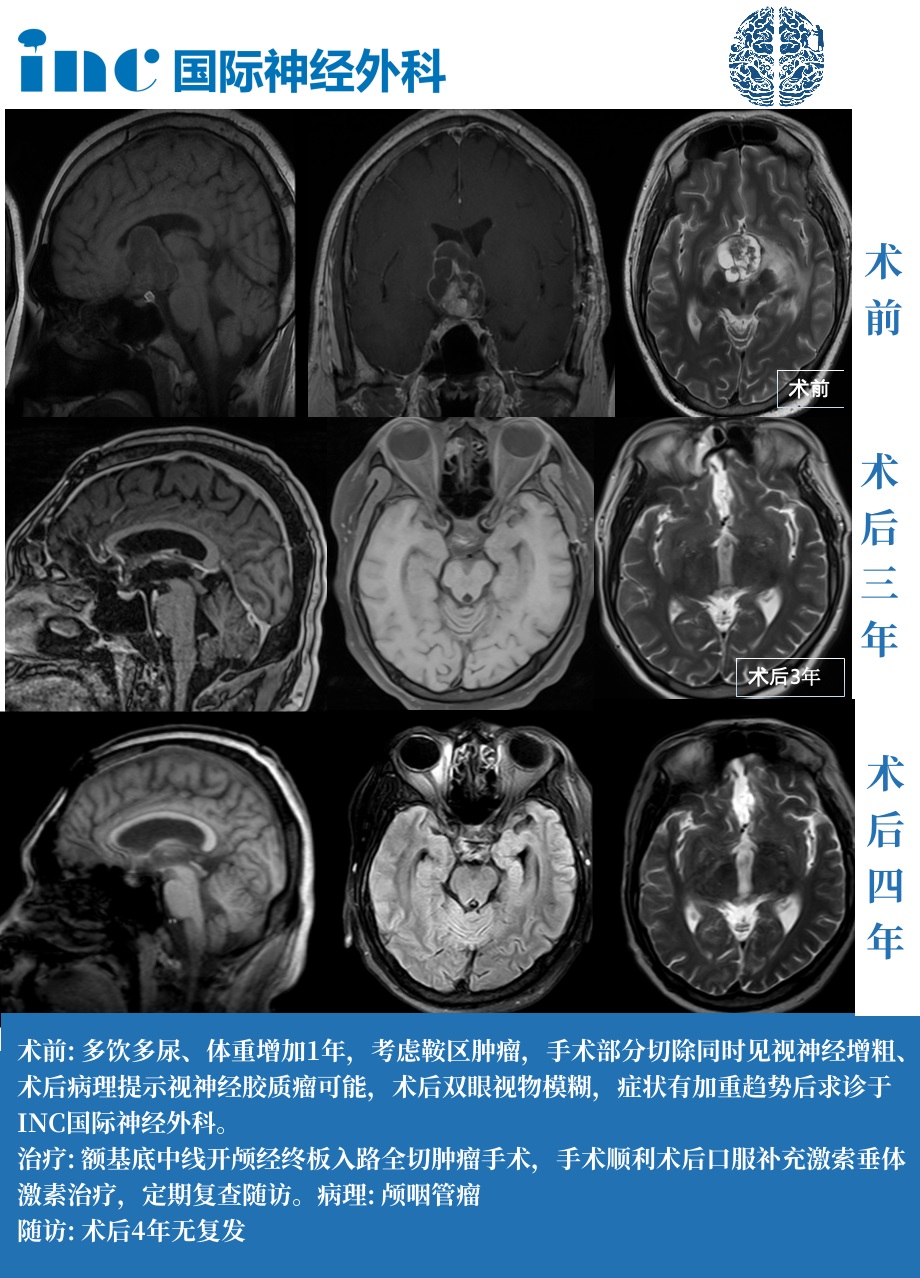

高先生知道,这个肿瘤不会就此停止生长。复查显示:鞍上病变实性部分可见团片不均匀强化影,囊性区见囊壁强化影,整体大小约31*32*40cm。考虑鞍区术后状态,考虑颅咽管瘤残留。

终于,他们决定完全铲除这个让他失去正常生活的颅咽管瘤。2019年11月,INC德国巴特朗菲教授主刀,进行了高难度的全切手术,成功地将颅咽管瘤完全切除。

手术结果:显微镜下全切肿瘤,手术顺利。病理结果显示颅咽管瘤。

4年过去了,他坚持复查,没有复发,免去了需要反复再放疗或手术的烦忧。